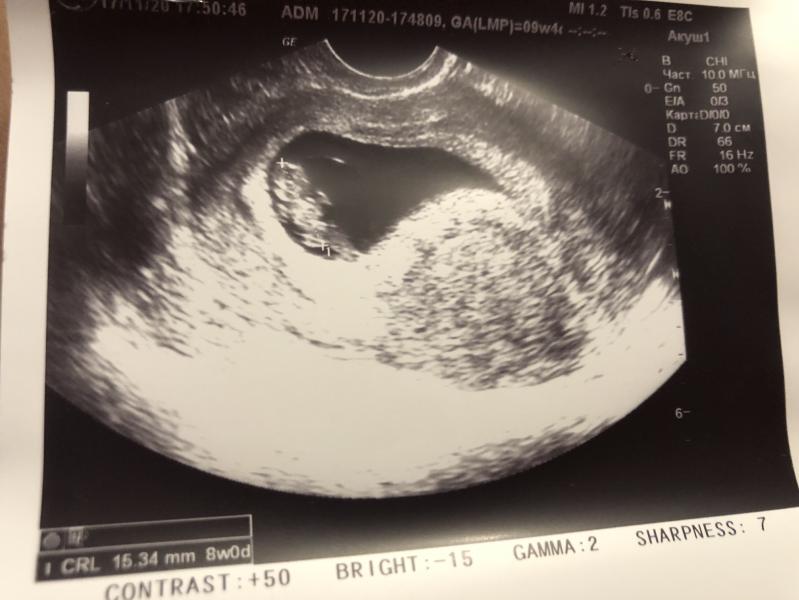

У нас сегодня радость 😍третье узи и наконец-то показался эмбрион и сердечко было слышно , даже видно как бьется. Это такое счастье после стольких дней ожидания . 🥰

Сейчас попробую точно по датам . 21 октября был положительный тест и несколько дней задержки , срок поставили 4-5 недель . На узи была 30 октября ничего не видно сказали что разница со сроком по месячным почти две недели и надо ждать , делали второе через неделю числа 6го ноября плохо видно и не слышно сердце . И ещё ждала 1,5 недели где то , и вот на третьем узи все увидели и услышали .